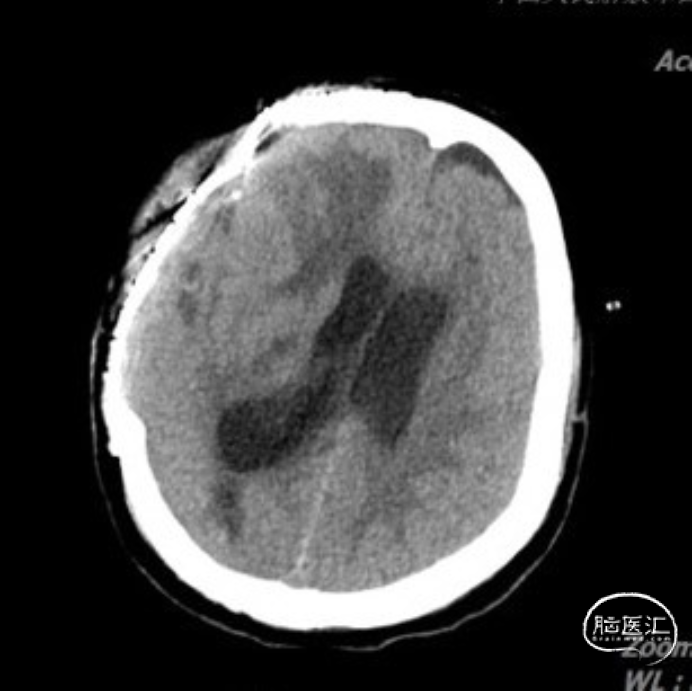

入院头颅CT:右侧颅骨缺失,左侧硬膜下积液,中线右偏明显。

术后因为左侧硬膜下引流管欠通畅,患者逐渐出现意识障碍,复查头颅CT:左侧硬膜下积液增加,中线右偏。积极疏通引流管后患者意识障碍明显好转,复查头颅CT提示:硬膜下积液减少,中线回归明显。